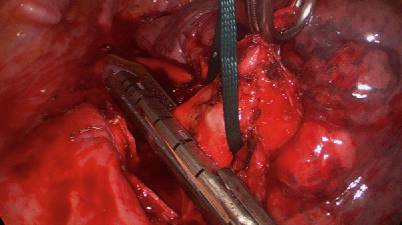

Abb. 4

Absetzen des linken Hauptbronchus zur Komplettierungspneumektomie. Es besteht ein Z. n. Oberlappenresektion links, erkennbar an der Klammernaht in der Lungenfasszange